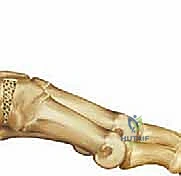

جراحة كوتون هي عبارة عن إجراء جراحي دقيق يتضمن عمل شق أو قطع في العظم الإسفيني الإنسي (Medial Cuneiform)، ثم فتح هذا الشق لتكوين فجوة على شكل "وتد" (Wedge). يتم بعد ذلك ملء هذه الفجوة بطعم عظمي (Bone Graft) وتثبيتها. النتيجة المباشرة لهذا الإجراء هي دفع مشط القدم الأول إلى الأسفل (Plantarflexion)، مما يعيد القوس الداخلي للقدم ويصحح تشوه مقدمة القدم الأروح.

4. فتح الوتد العظمي (Opening the Wedge)

بمجرد إجراء القطع، يتم إدخال أداة دقيقة تسمى مباعد الصفيحة (Lamina Spreader) أو أزاميل متدرجة لفتح الشق العظمي تدريجياً. يتم فتح هذا الوتد حتى يتم دفع مشط القدم الأول للأسفل ليصل إلى المستوى المطلوب (الوضع المحايد أو الانثناء الأخمصي الطفيف) مقارنة بباقي أمشاط القدم. يتم التحقق من التصحيح ميكانيكياً وبصرياً داخل غرفة العمليات.